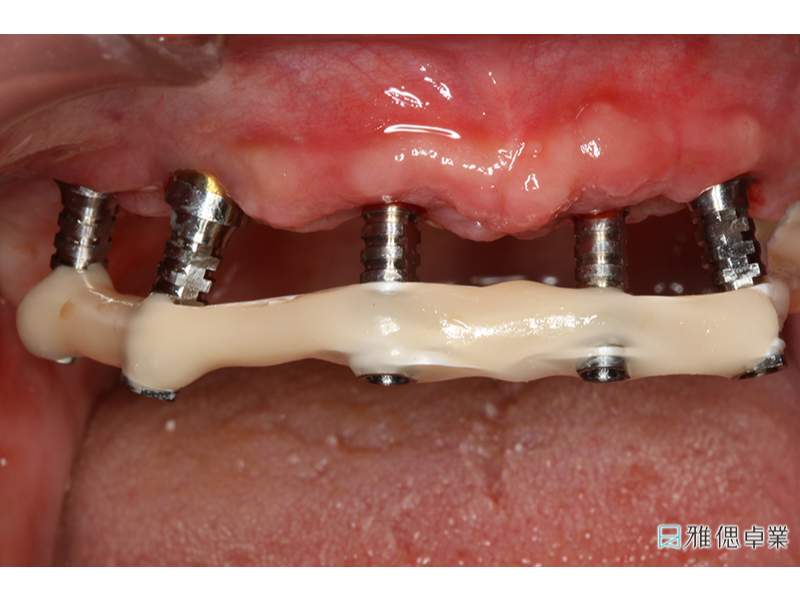

當日即可完成All on 6臨時假牙

All on 6植牙當天可立即裝戴臨時假牙

口內取定位模型